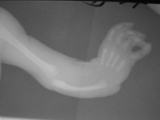

Multiple exostoses-forearms

Multiple exostoses-forearms